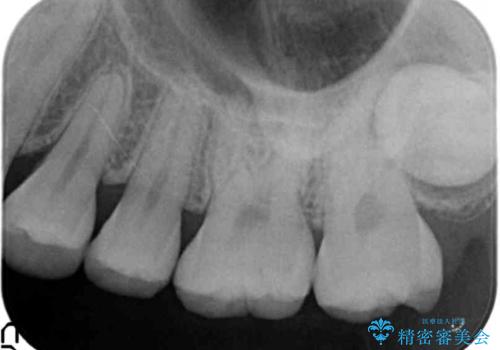

気づかなかった奥歯のう蝕 セラミックインレー 20代女性

- クリーニングを希望され来院された患者様です。

精査したところ、奥歯にう蝕を認めました。

症状がなく気がつかなかったそうで、虫歯があったことに驚かれていました。

患者様のご希望により、う蝕を丁寧に除去したのちセラミックインレーによる修復を行いました。

インレーの種類:セラミックインレー(e-max press)